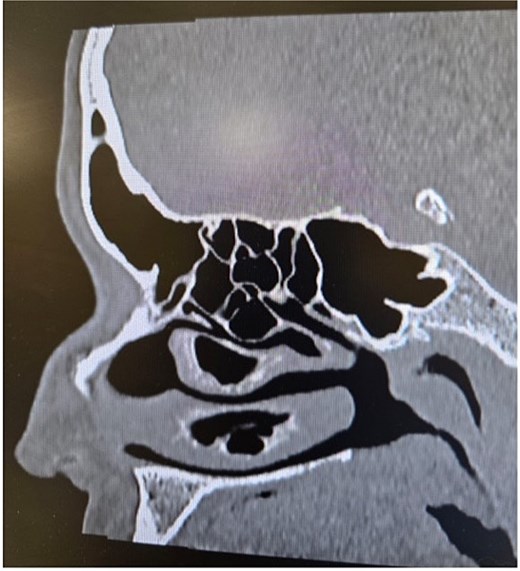

Clinical examination, including anterior rhinoscopy and nasal endoscopy, revealed a midline nasal septum and bilateral hypertrophy of the inferior and middle turbinates, with otherwise normal nasal mucosa. A CT scan of the paranasal sinuses in the coronal plane demonstrated bilateral pneumatization of the middle turbinates consistent with CB. Additionally, the right inferior turbinate was pneumatized, with communication to the ipsilateral maxillary sinus (Figs 1 and 2).

Paranasal sinus CT scan in the coronal plane showing bilateral concha bullosa in the superior turbinates and pneumatization of the right inferior turbinate (inferior concha bullosa).